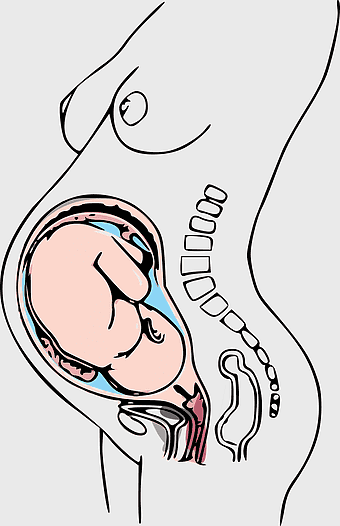

embryo development illustration, fetal growth stages, human embryogenesis process, pregnancy anatomy diagram, prenatal development visuals, uterine environment depiction, fetal positioning analysis -

828x1280px

pregnancy illustration, caesarean section diagram, prenatal care visual, morning sickness depiction, fetal development art, maternity health graphic, pregnancy anatomy sketch -

579x1155px